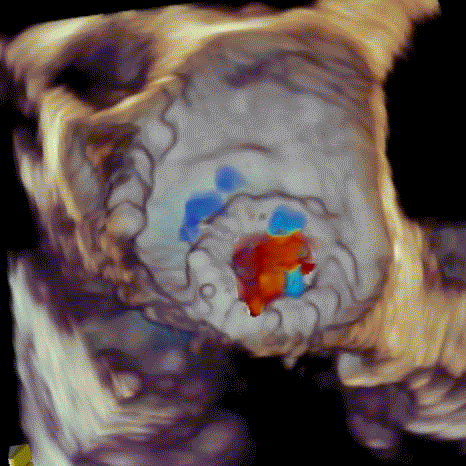

球扩瓣释放

瓣中瓣植入前

二尖瓣重度反流

瓣中瓣植入后

无明显瓣中及瓣周反流